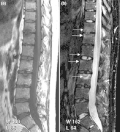

T2-weighted MRI (sagittal) of index finger in PsA (mutilans form) showing probable erosion (increased signal) at base of the middle phalanx (long thin arrow), synovitis at the proximal interphalangeal joint (long thick arrow), soft tissue edema (short thick arrow), and diffuse bone edema (short thin arrows) of the proximal phalanx. -